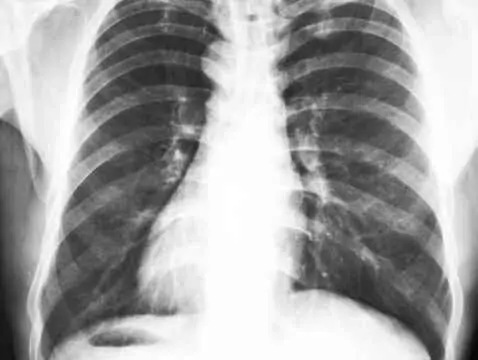

Wada ta należy do wrodzonych zniekształceń ściany klatki piersiowej. Polega na nadmiernym uwypukleniu mostka do przodu.